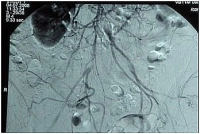

Oclusão aórtica alta com estenose subtotal da bifurcação ilíaca, oclusão da AIC direita e trombose na AIE esquerda (estágio clínico Fontaine bilateral IIb).

-> TASC II D, portanto recomendação para revascularização aberta

DSA intra-arterial pré-operatória